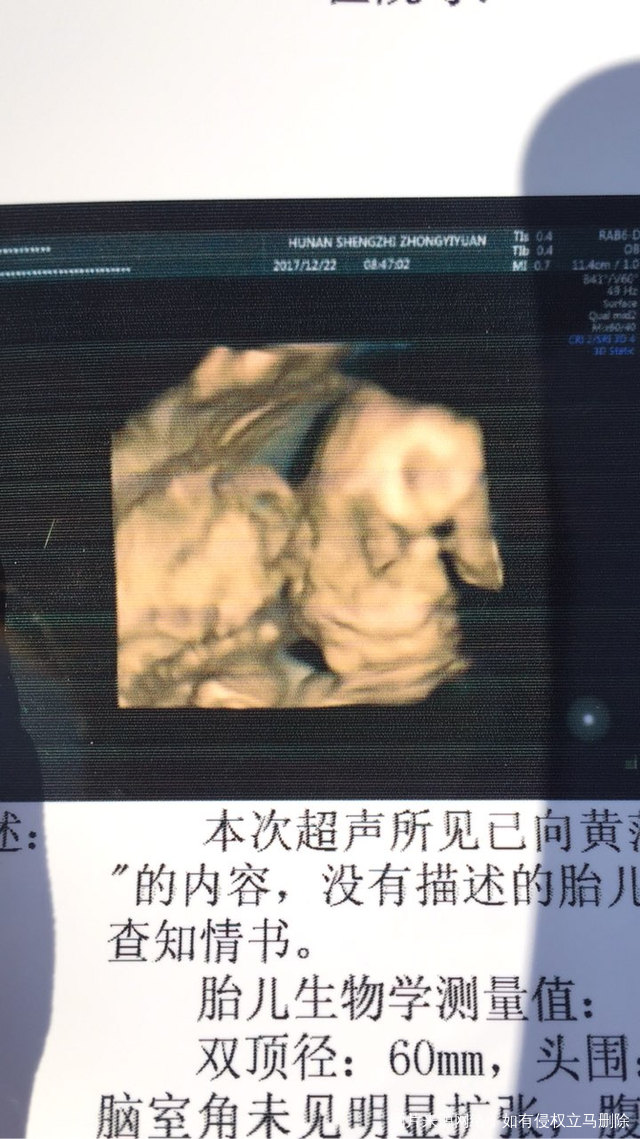

我老公说这个崽崽像猪八戒,我妈妈看了说像他[大笑][大笑][大笑][大笑]2017-12-23 18:26:02